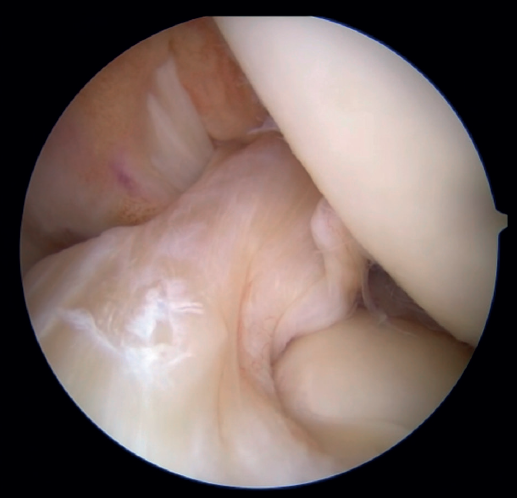

The patient is placed in the supine position and the leg is draped and prepared for knee arthroscopy at the surgeon's discretion, as if an ACL plasty were to be performed. The anterolateral and anteromedial portals are established as usual, and the joint is explored. On exploring the central compartment, it should be confirmed by direct vision and also palpation that the lesion is proximal and that the tissue quality is good; if the tissue is friable and tears easily, repair is not indicated. If the ACL remnant is attached to the PCL, it must be dissected so that the ACL is free and can be manipulated to its insertion site. A blunt shoulder arthroscopy periosteotome is best used for this, although a synoviotome, vaporizer or plasma applicator could also be used, as long as care is taken not to break or burn the tissue and render it non-viable. If there are concomitant meniscal or cartilage lesions, they should be treated earlier in order to avoid forced varus and valgus positions after the repair is completed.

Once a good view of the central compartment is obtained, the area of the femoral footprint of the ACL is prepared to leave exposed bone, and microperforations are made in the medial wall of the lateral condyle to leave a bleeding bed to favor healing of the ligament (Figure 3). These microperforations can be made using specific instruments or with the implant punch. The advantage of using the punch is that the implant insertion site can be prepared at the same time, and only one instrument is used for the entire process (Figure 4). This step can be done after the suture has been prepared in the ligament, although doing it beforehand avoids the threads from standing in the way. The ideal point for fixation is just anterior to the native ACL footprint, although if the tear is partial or corresponds to Sherman I, it can be taken to the anatomical footprint without difficulty.